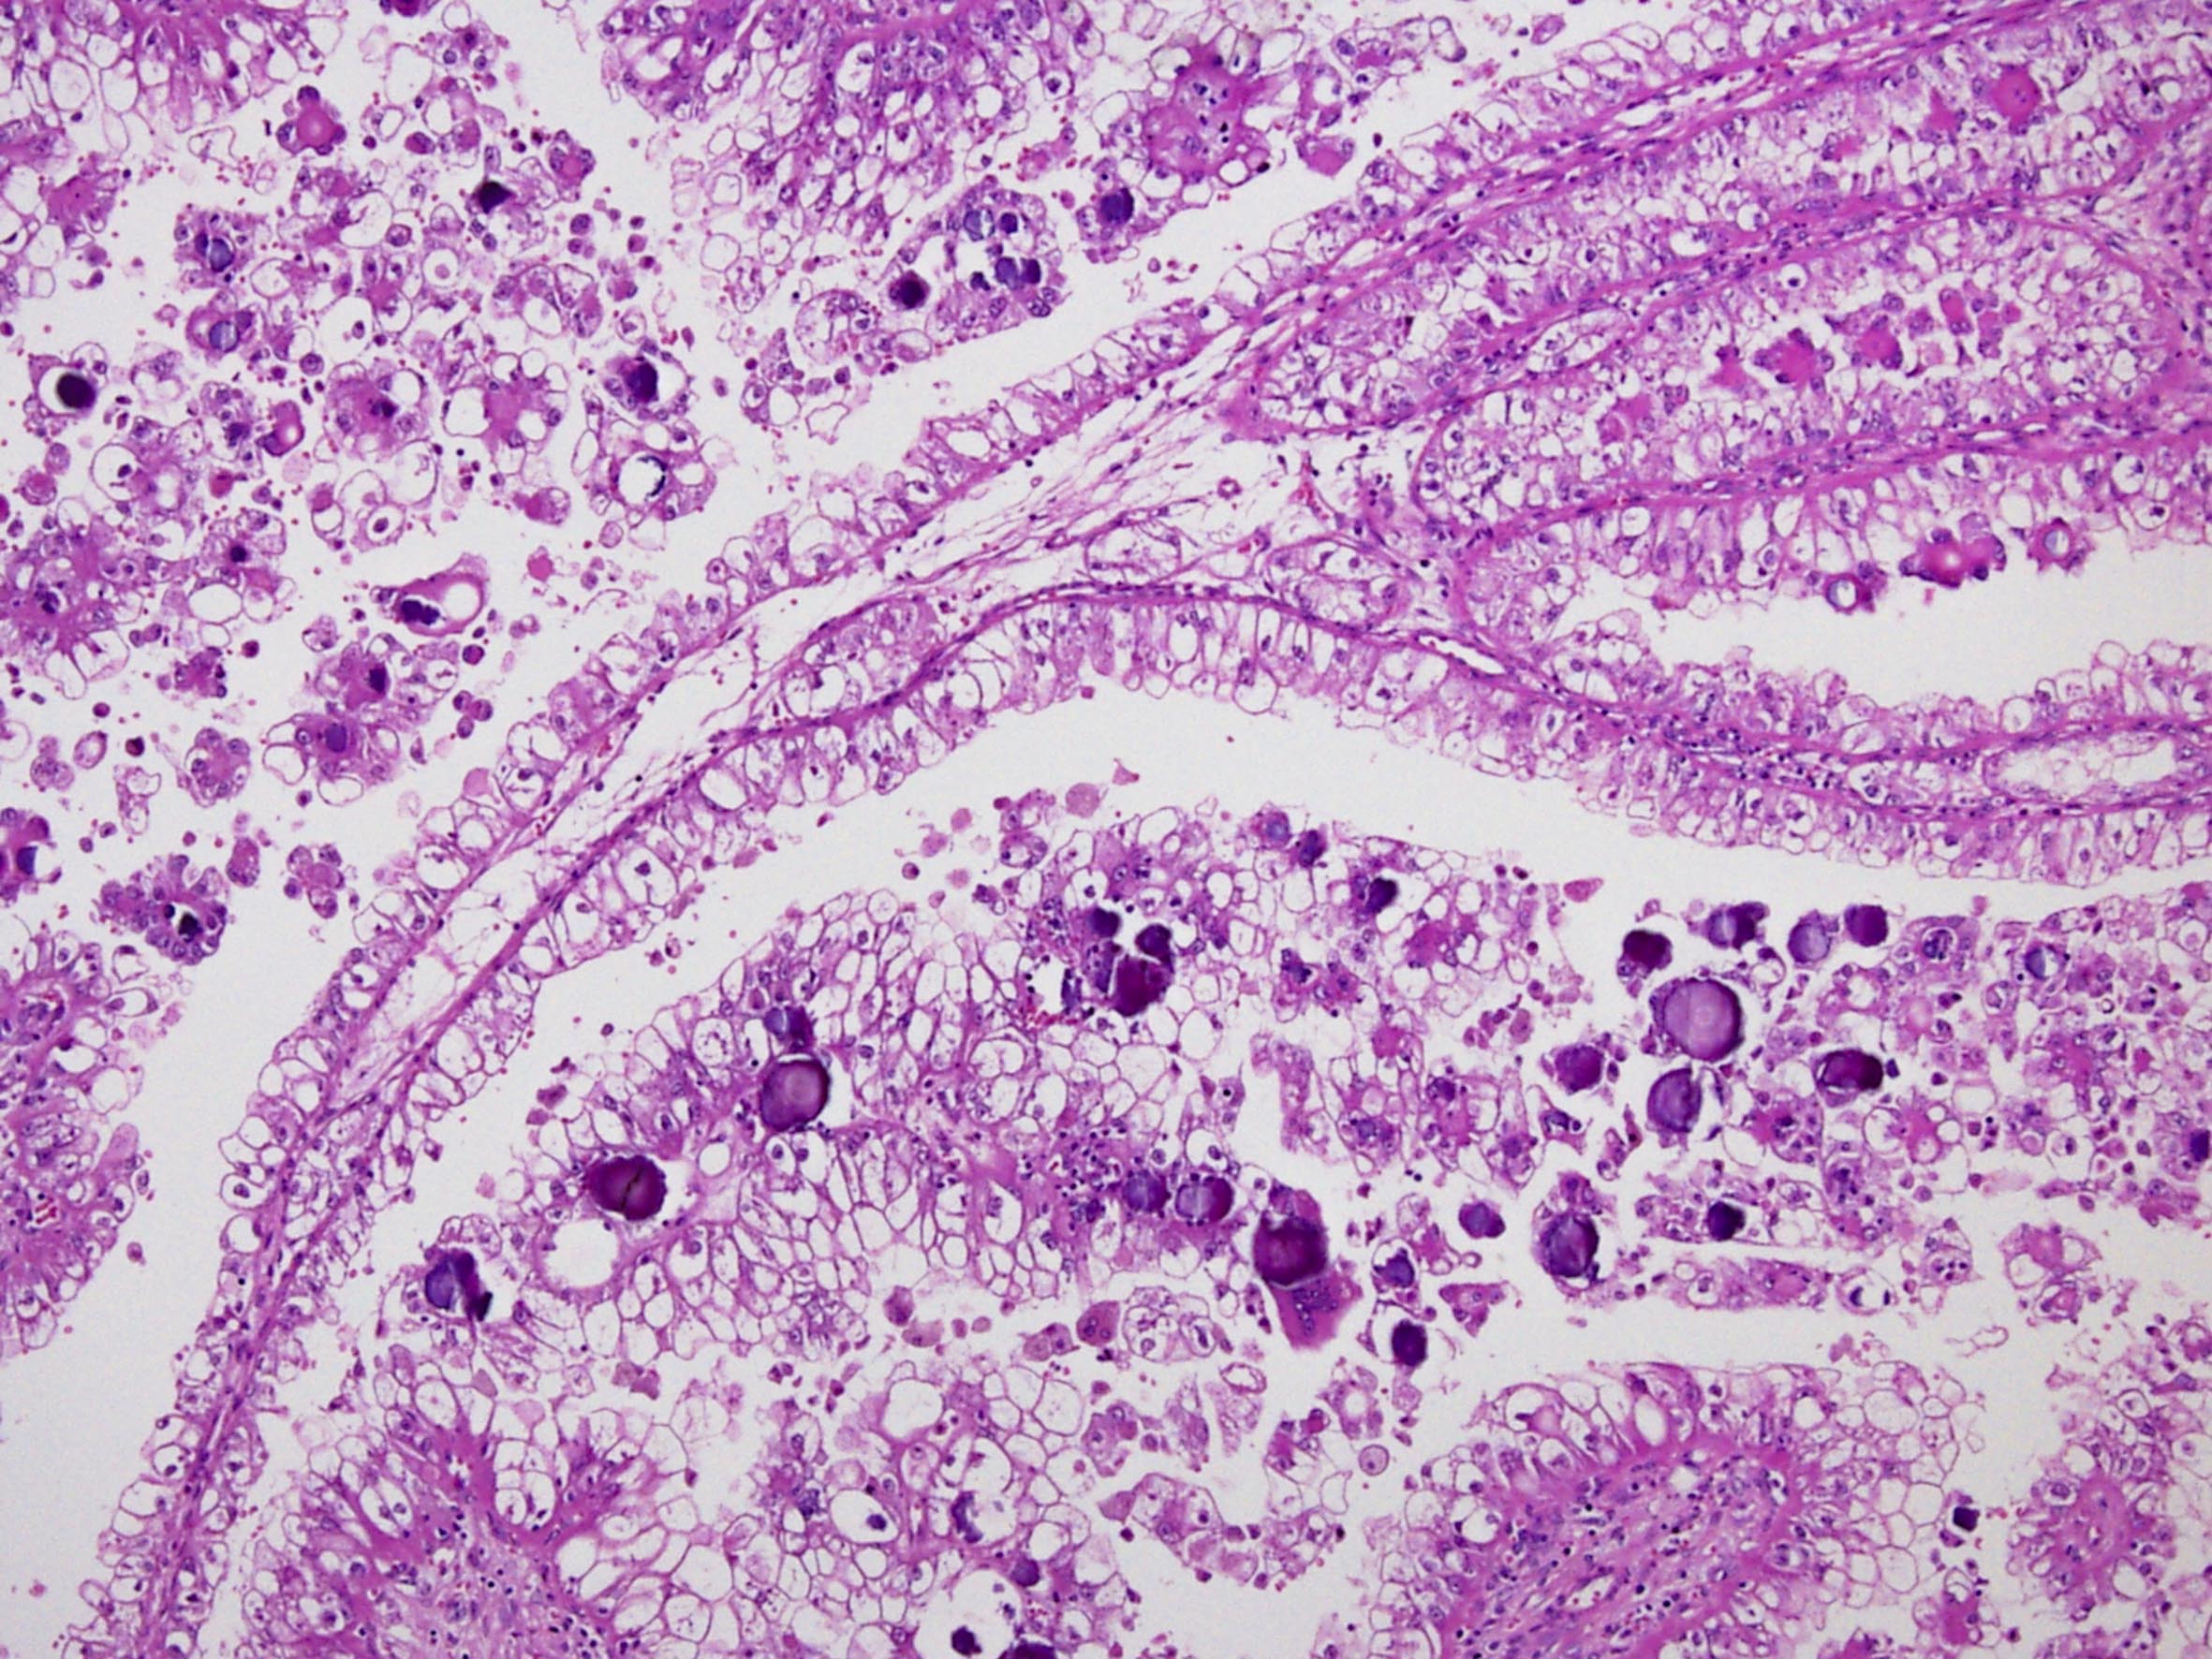

Classification of renal tumors

Case ID: 274